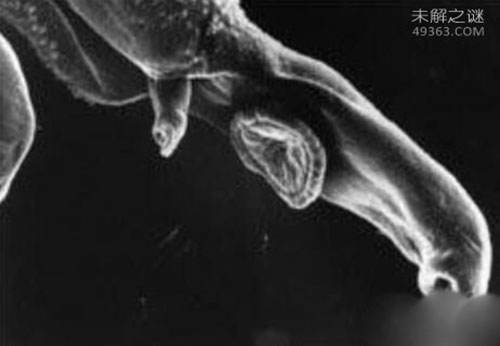

尾蚴血吸虫尾蚴属叉尾型,由体部及尾部组成,尾部又分尾干和尾叉。体长100~150μm,尾干长140~160μm,尾叉长50~70μm。全身体表被有小棘并具有许多单根纤毛的乳突状感觉器。体部前端为特化的头器(headorgan),在头器中央有一个大的单细胞腺体,称为头腺。

口位于体前端正腹面,腹吸盘位于体部后1/3处,由发达的肌肉构成,具有较强的吸附能力。在尾蚴体内中后部有5对单细胞钻腺(penetrationgland),左右对称排列,其中2对位于腹吸盘前,称前钻腺,为嗜酸性,内含粗颗粒;3对位于腹吸盘后,称后钻腺,为嗜碱性,内含细颗粒。前后5对钻腺分别由5对腺管向体前端分左右两束伸入头器,并开口于顶端。